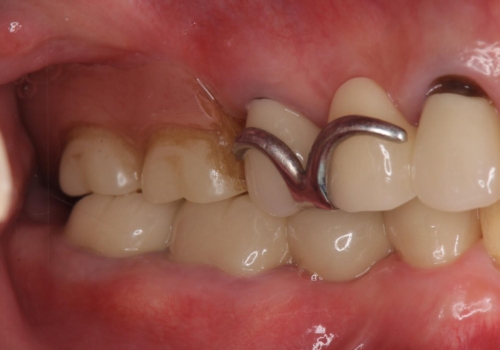

- 他院で右下小臼歯が保存不可能と言われ来院。当院の判断でも残念ながら抜歯となり、欠損部は抜歯後ブリッジにしました。右下奥2本が連結されていたため、そこは各々切り離した形で被せ物のやり替えも行っています。

抜歯後3か月ほど仮歯で生活していただき、欠損部の歯肉の状態が安定してからブリッジを入れています。